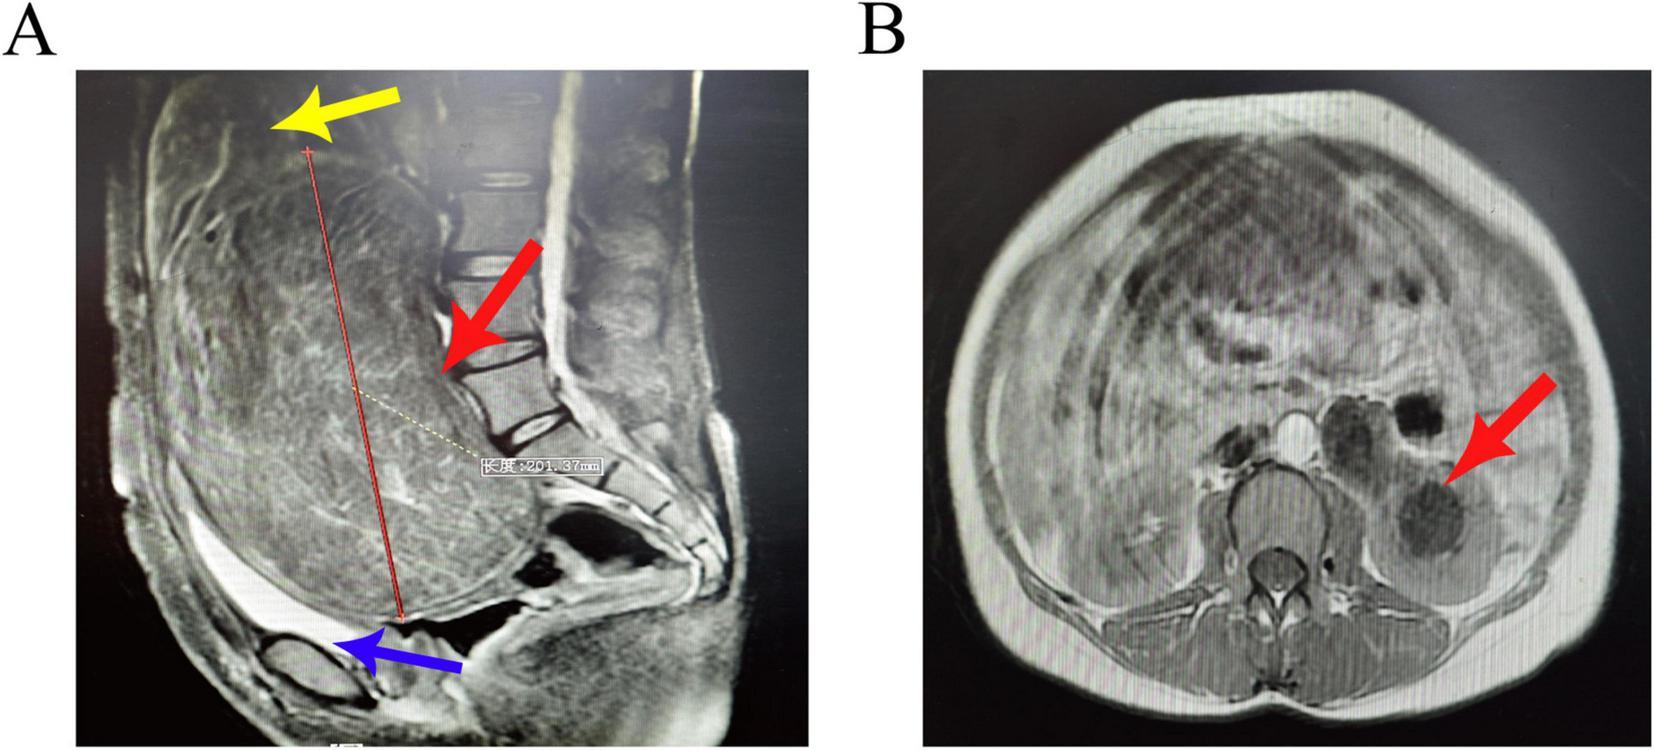

Pelvic MRI: A large mass is observed posterior to the cervix, with well-defined margins, measuring approximately 19.8 × 19.7 × 17.2 cm. The uterine body is elevated due to pressure, and there is elongation of the cervical canal. Multiple rounded short T2 signal lesions are noted in the myometrium, exhibiting mild enhancement. The bladder is compressed and displaced anteriorly and downward (Figure 2A). The left renal pelvis and ureter are dilated (Figure 2B), with the distal segment of the left ureter showing unclear visualization. Some bowel segments in the pelvis are indistinct from the mass. Impression: A large space-occupying lesion posterior to the cervix, with a high likelihood of fibroids, indicating low-grade obstruction of the left urinary tract, multiple uterine fibroids, and heterogeneous signal in the uterine fundus and anterior wall, raising suspicion for adenomyosis.

FIGURE 2

(A) Sagittal view of the pelvic MRI shows a large mass posterior to the cervix with well-defined margins, measuring approximately 20 cm. Multiple rounded short T2 signal lesions are observed in the myometrium, exhibiting mild enhancement (red arrow). The uterine body is elevated due to pressure, and there is elongation of the cervical canal (yellow arrow). The bladder is compressed and displaced anteriorly and downward (blue arrow). (B) Axial view demonstrates dilation of the left renal pelvis and ureter (red arrow).